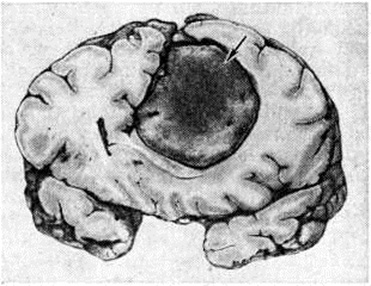

Рис. 1.

Фронтальный срез головного мозга с парасагиттальной менингиомой, исходящей из серповидного отростка (указана стрелкой).